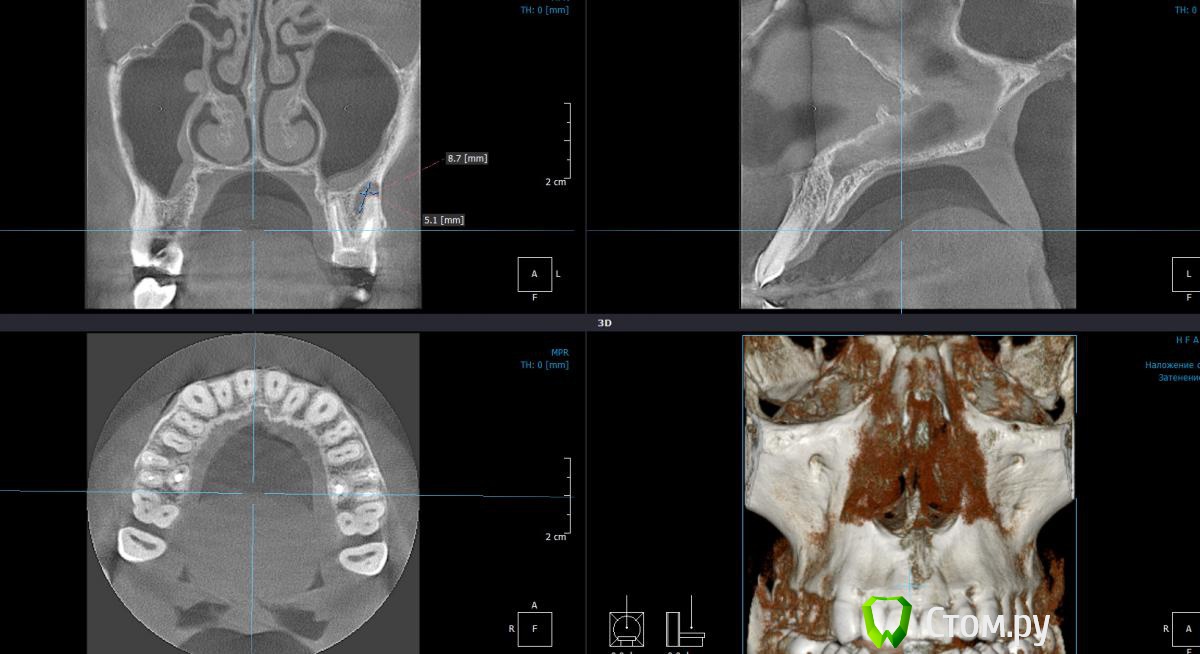

Dtm Опубликовано 1 марта, 2014 Автор Поделиться Опубликовано 1 марта, 2014 Подниму немного свою тему - сделал наконец то КТ, кажется я не ошибался в своих подозрениях на обе верхние 6-ки, что скажут уважаемые доктора? Ссылка на комментарий

Dtm Опубликовано 3 марта, 2014 Автор Поделиться Опубликовано 3 марта, 2014 Спасибо! На КТ видно что верхушки корней 6 контактируют с ВЧ пазухой - насколько велик риск при перепломбировании (я правильно понял?) вывести пломбировочный материал за верхушку корня в пазухи в данном случае? Ссылка на комментарий

Dtm Опубликовано 3 марта, 2014 Автор Поделиться Опубликовано 3 марта, 2014 Согласен, но для меня как пациента это имеет решающее значение - последствия могут быть неприятные. Может быть безопаснее удалить с имплантацией в перспективе? На левой 6 явно киста у корня? Насколько реально ее пролечить и как, просто сменить пломбу думаю не все, терапия какая то нужна в процессе, я имею ввиду вскрыть, ввести лекарство например? Ссылка на комментарий